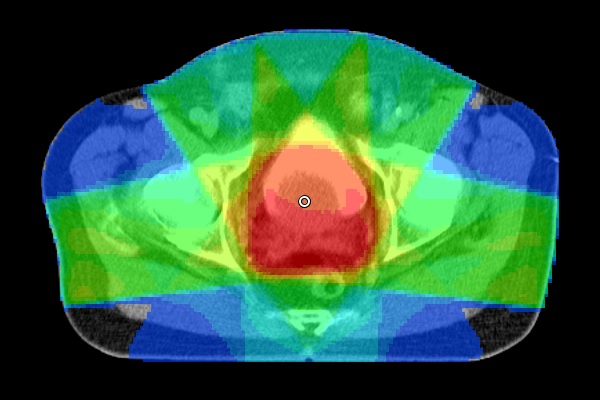

Radiotherapy planning software is responsible for generating contours for protection of risk organs and contours for tumor areas. To exemplify this process, below are the contours and radiations for you to interact with! Change the position of the slide (green circle) and check the outlines and rays (radiation) generated with SIPRAD for a radiotherapy treatment.

Generation of radiation doses in body regions using 5 fields.